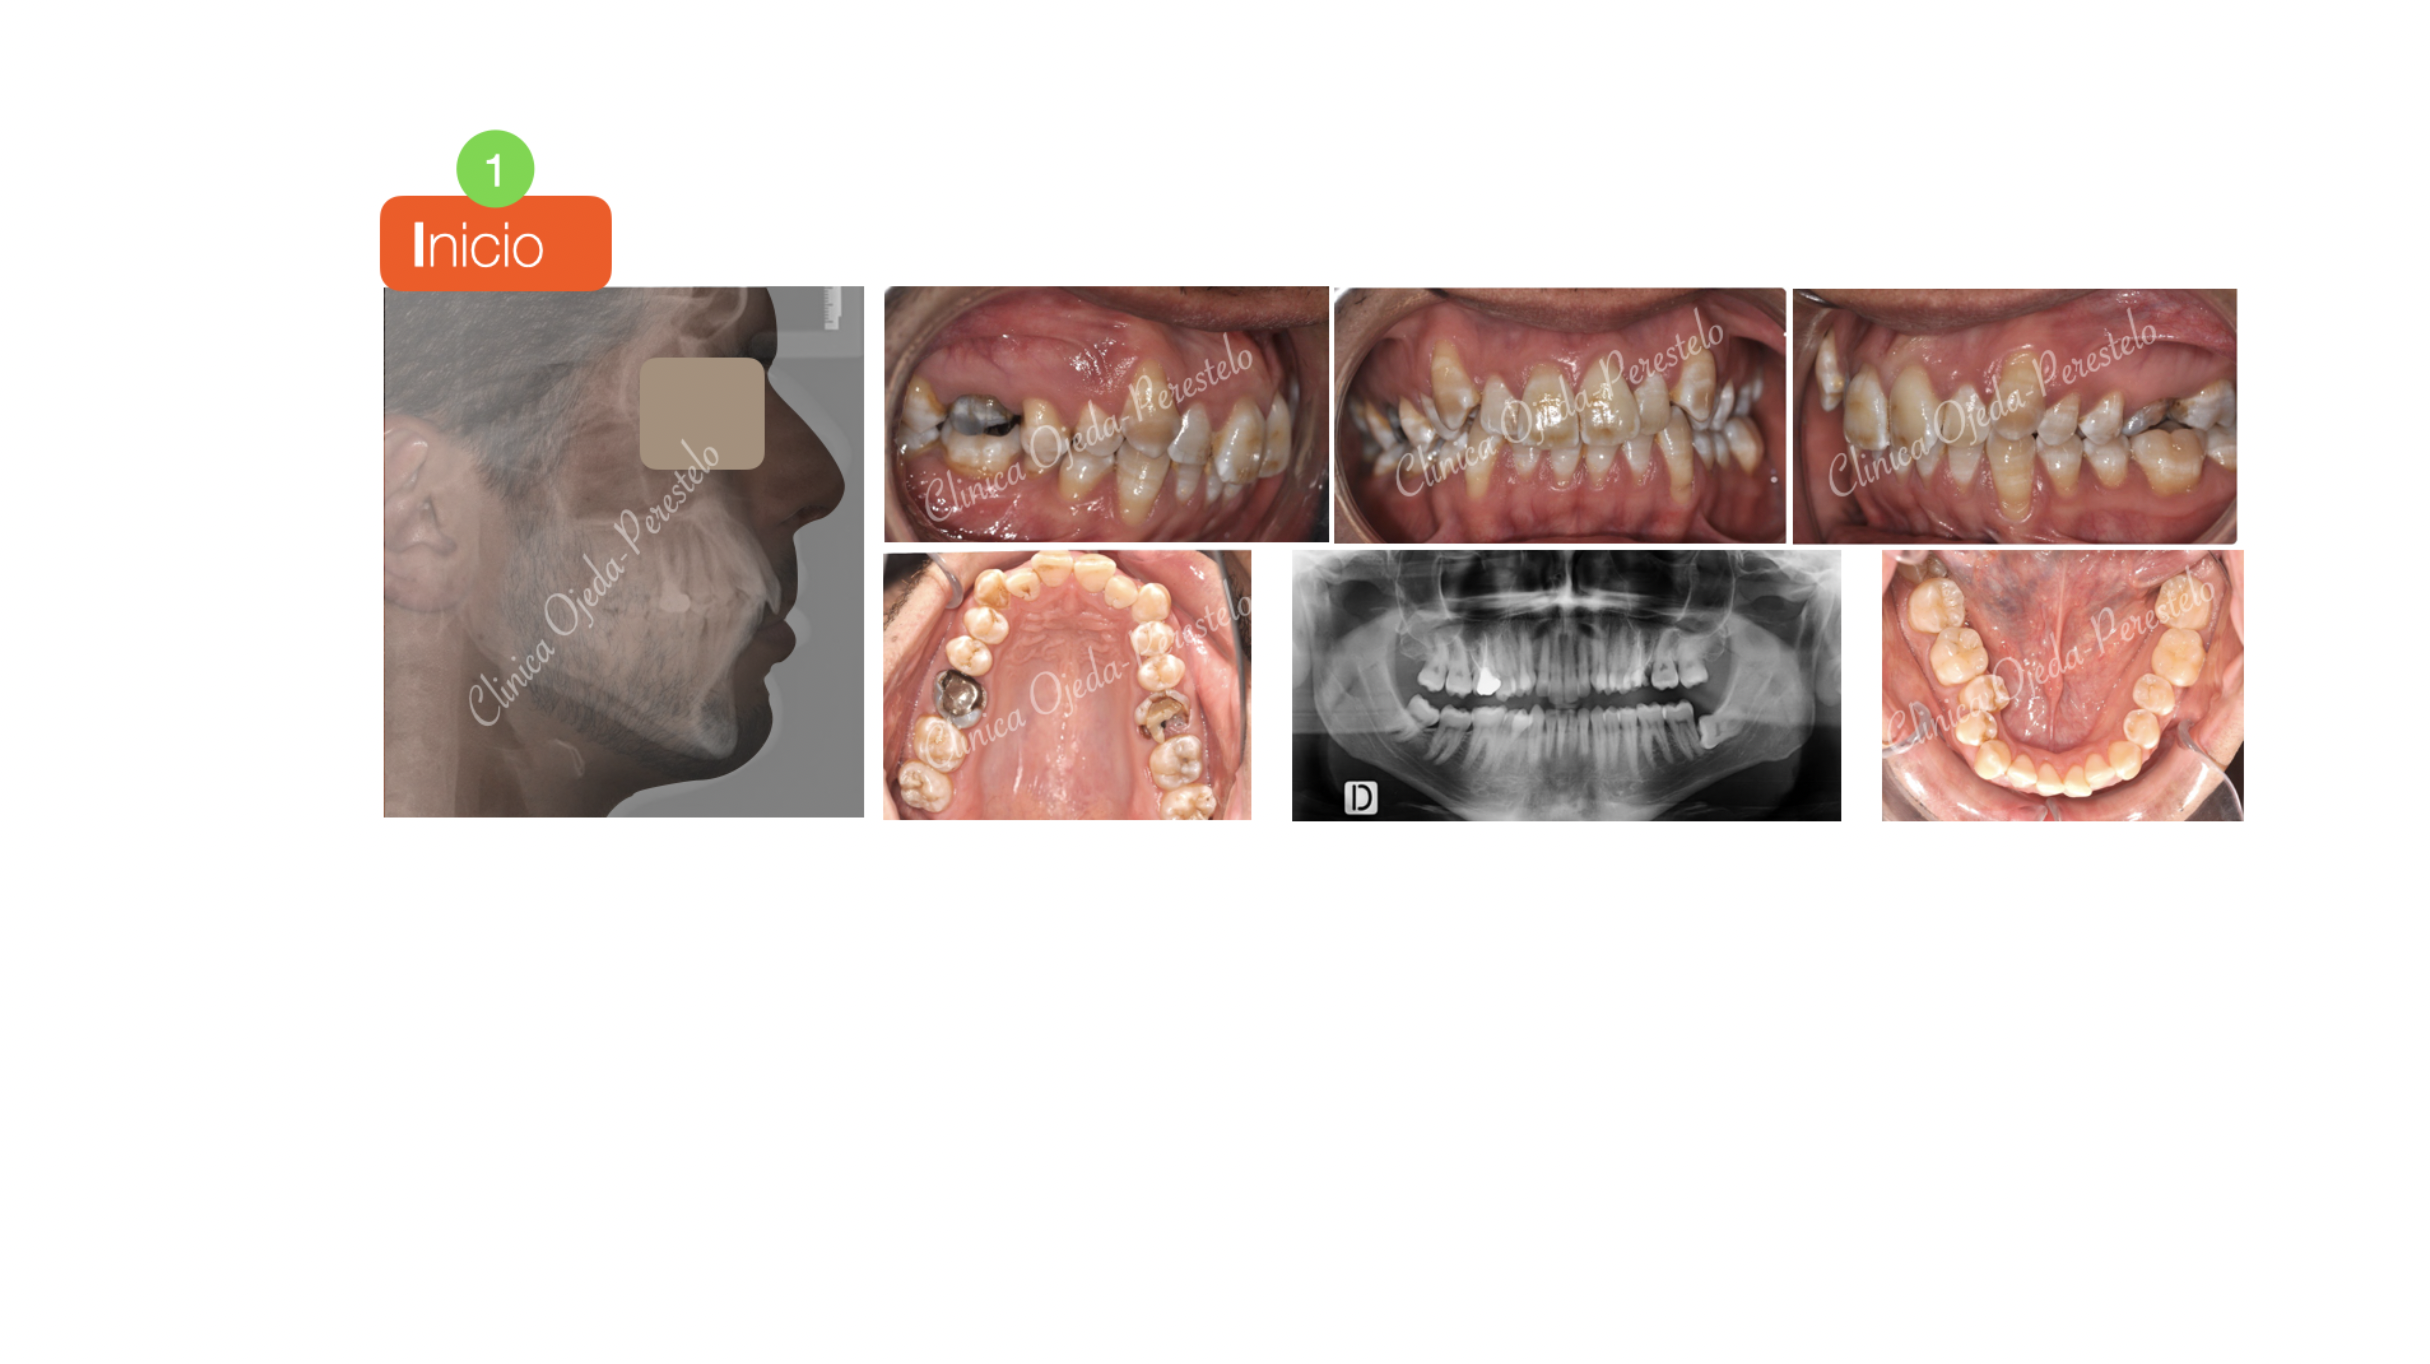

Apiñamiento severo con molares con mal pronóstico

Paciente tratado con brackets de autoligado pasivo (Sistema Damon) donde hemos alineado y nivelado desarrollando las arcadas. Este caso presenta la particularidad de haberse realizado las extracciones de los molares superiores (16,26 ) ya que los mismos  presentaban un mal pronóstico.

Quisieramos destacar cómo en la actualidad podemos realizar extracciones de molares en mal estado y cerrar dichos espacios SIN necesidad de colocar implantes o puentes y sin comprometer la estética ni la amplitud de la sonrisa.